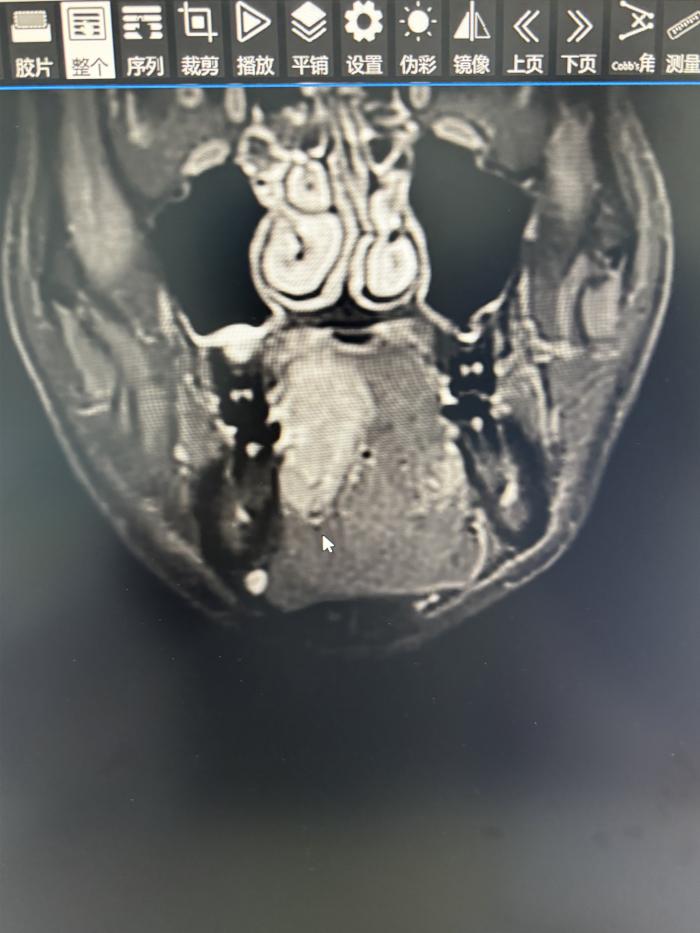

42岁的何先生长期咀嚼槟榔,近两个月以来,发现右侧舌腹肿痛不适,遂前往湘南学院附属医院就诊。经口腔科完善相关检查,确诊了何先生罹患舌癌。

舌恶性肿瘤是口腔恶性肿瘤里发病率占比最高的,也是最容易发生转移的,目前最适宜的治疗手段就是尽早发现、尽早治疗,以防转移后手术效果欠佳。

口腔科团队为何先生展开了详细的术前讨论,并想方设法从各方面为患者节约治疗费用,做好了充分的术前准备后,为何先生实施了舌颌颈联合根治术+股前外侧肌皮瓣转移修复术。

此项手术是一项高难度、极具挑战性的手术,需要完成颈部淋巴结的切除、口腔恶性肿瘤的切除、制备皮瓣、吻合血管及颌面部重建四大步骤,每一步都需要耗费医务人员大量的精力和时间,常规需要12小时左右才能完成。